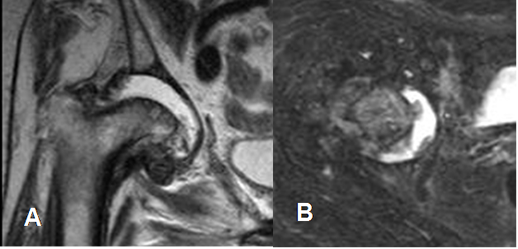

Fig 8. Artropatía degenerativa en cadera.

A: Rx AP de cadera. B: RM coronal en T2 y C: RM coronal en STIR. Pérdida del espacio articular, esclerosis y lesiones radiolúcidas en la Rx e hiperintensas en la RM, sobre la cabeza femoral y el acetábulo, que corresponden a quistes subcondrales. (Flechas).